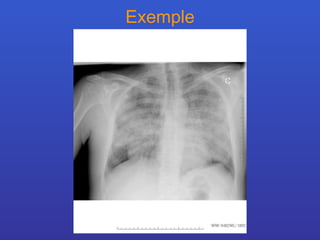

Exemple